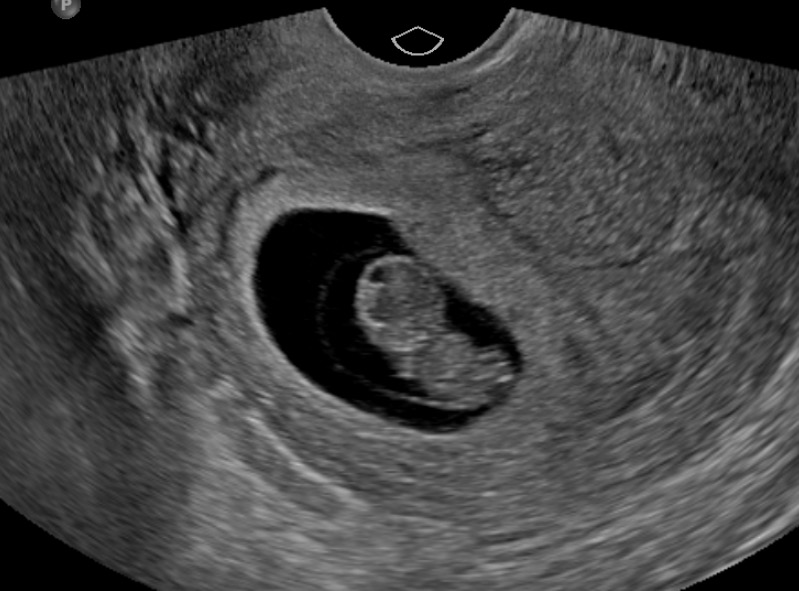

임신 증상들은 힘들지만, 사랑하는 뱃속의 아기를 보며 힘내고 기쁘게 참자!!

마무리는 사랑하는 우리 아기로! ❤︎